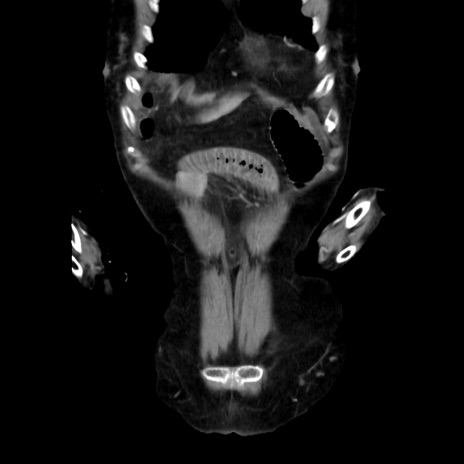

症例40(冠状断像)

【症例】90歳代女性

【主訴】腹痛・嘔吐

【現病歴】 食欲低下、嘔吐があり昨日他院受診。肺炎と診断され入院となる。入院後より腹部全体に圧痛あり。胃管留置され経過みていたが、症状持続するため、

当院転院となる。

【既往歴】胸椎圧迫骨折、胆石症

【身体所見】腹部:中央に激痛あり、圧痛あり、反跳痛不明

【データ】WBC 17100、CRP 18.82

他院CT

横断像